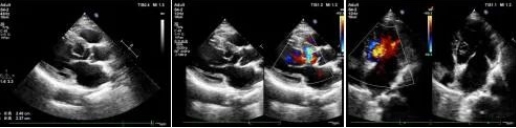

市中心医院超声科成功诊断一名罕见先心脏病患者

3月9日,乐鱼手机站入口超声科主治医师魏锦为患者进行超声动态检查。

据了解,患者李某,男,63岁,因突发胸闷气短就诊于乐鱼手机站入口心血管内科门诊。门诊医生接诊进行相关查体后,怀疑患者心脏突发急症,心电图T波异常,遂建议行超声心动图检查。

在超声动态影像检查下主治医师魏锦发现主动脉瓣环下约10mm处见线样强回声突入左室腔,为给出明确诊断,超声科心脏血管组医师共同对患者进行诊断,凭借丰富的实践经验,最终诊断结果为“左室囊袋状结构,考虑内膜撕脱”,提示患有“先天性心脏病主动脉左冠窦窦瘤形成伴破裂入左室”这种罕见病症。乐鱼手机站入口超声科在第一时间为患者制定最佳治疗方案提供了保障。

患者遂转往空军军医大学西京医院手术治疗。术中实际情况也证实了术前的超声诊断。

“这种疾病非常罕见,诊断过程中想到这个病很关键!”西京医院相关领域专家对乐鱼手机站入口超声诊断水平高度的认可,也展现我院超声诊断水平有了飞跃式的提高。